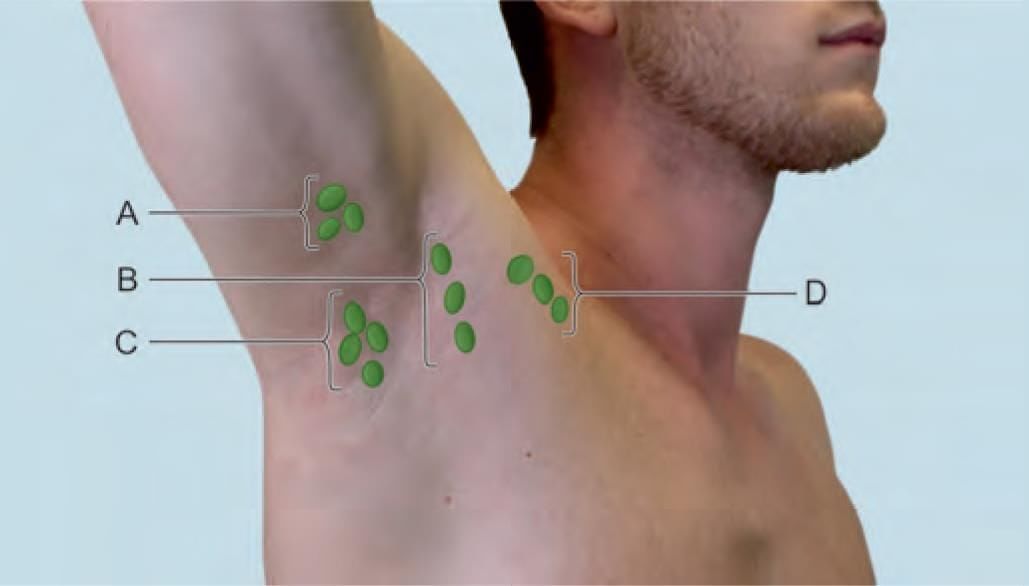

Choose the CORRECT matching pair for axillary lymph nodes in the given diagram: (INI-CET Nov 2022)